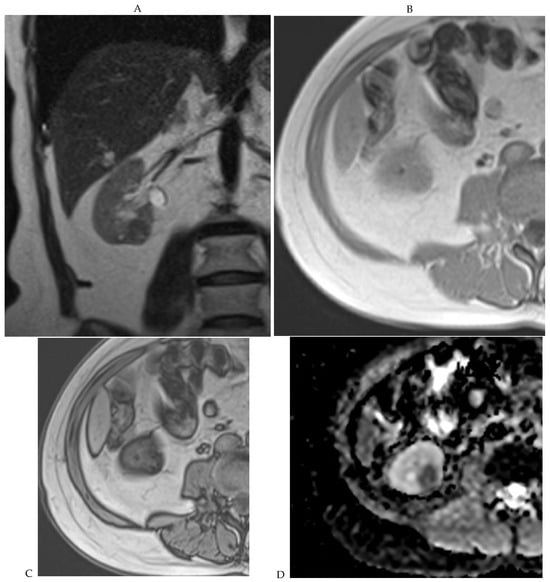

Figure 5.

Clear cell renal cell carcinoma in the right kidney of a 52-year-old-man. (A) Coronal T2-weighted fast SE image shows a large heterogeneous mass with areas of high signal intensity compared with renal parenchyma. Transverse in-phase (B,C) opposed-phase MR images show a subtle signal loss on the opposed-phase image. (D) The ADC map is heterogeneous with predominant areas of restriction of tumor diffusion. Transverse gadolinium-enhanced T1-weighted gradient-echo spoiled MR images in (E) corticomedullary, (F) nephrographic, (G) and delayed phase images show intense and rapid peripheral enhancement during the arterial and nephrographic phases followed by a rapid washout of contrast on the delayed phase. Central necrotic areas do not enhance. (H) Macroscopic view of the lesion after radical nephrectomy. The lesion appears heterogeneous. Courtesy of Pr S. Ferlicot, Department of Pathology, Bicêtre Hospital.